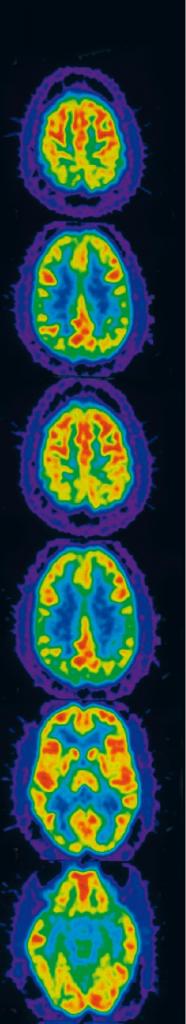

Мозговая библиотека

Ученые, работавшие с Генри, еще много лет назад поняли, как важно будет получить его мозг для подробного исследования — чтобы в точности узнать, какие участки были удалены при операции, что происходило с остальными тканями. Сюзан Коркин объяснила это пациенту и его опекуну, и в 1992 году были подписаны все необходимые документы. Десять лет спустя Коркин собрала исследователей мозга, специализирующихся в различных областях, чтобы обсудить, что нужно будет делать, когда Молашена не станет. Именно тогда было решено, что изготовлением срезов мозга будет руководить Джакопо Аннезе в Калифорнийском университете (Сан-Диего). После смерти Генри его мозг законсервировали и доставили в Сан-Диего, где специальным прибором были сделаны тончайшие срезы (70 микрон), которые можно рассматривать под микроскопом.* * thebrainobservatory. ucsd.edu/hm_live.php. Такие срезы дают гораздо более подробную информацию, чем магнитно-резонансная томография — один из основных современных методов исследования мозга. Оцифровку срезов и размещение их в интернете (всего их более 2400), а также создание подробной трехмерной карты мозга предполагается закончить к концу зимы. После этого все исследователи, когда-либо работавшие с Генри или изучавшие литературу о нем, смогут проверить свои гипотезы. Аннезе, руководитель проекта с амбициозным названием The Brain Observatory, который он окрестил «Библиотекой Конгресса для человеческого мозга», считает, что если собрать обширную коллекцию срезов мозга разных людей и дополнить их подробной информацией о донорах (от перенесенных ими заболеваний до привычек и характеров), это может привести к новым открытиям, не менее важным, чем те, что подарил нам Генри Молашен.